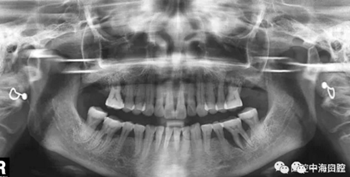

由于智齒的生長位置特殊,導致了拔除難易不同,如智齒出現(xiàn)橫著長或者靠近牙神經的話,則難度會較高,一般人只需拍個口腔全景片,但相對于智齒靠近神經管的情況,還可能需要拍CT,這都很考驗牙醫(yī)的技術。

拔牙非小事,請不要拿成本衡量牙醫(yī)的價值!

下面這兩張圖,據(jù)說拔牙費時1.5小時,收費14000元。